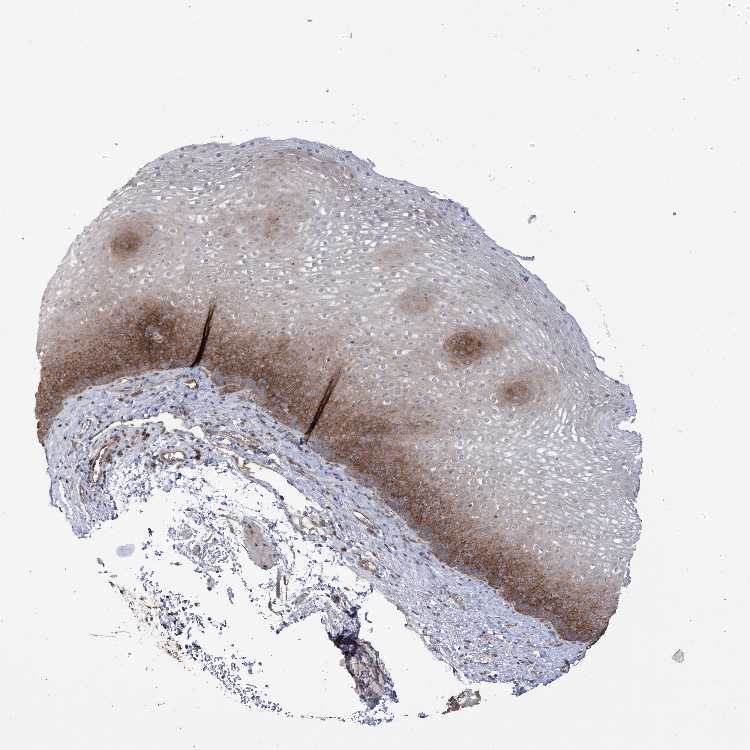

ESOPHAGUS - Antibody stainingi

Antibody staining in the annotated cell types in the current human tissue is reported as not detected, low, medium, or high, based on conventional immunohistochemistry profiling in selected tissues. This score is based on the combination of the staining intensity and fraction of stained cells.

Each image is clickable and will lead to virtual microscopy that enables deeper exploration of all samples and also displays staining intensity scores, fraction scores and subcellular localization as well as patient and tissue information for each sample.

Antibody HPA030145

Squamous epithelial cells Medium